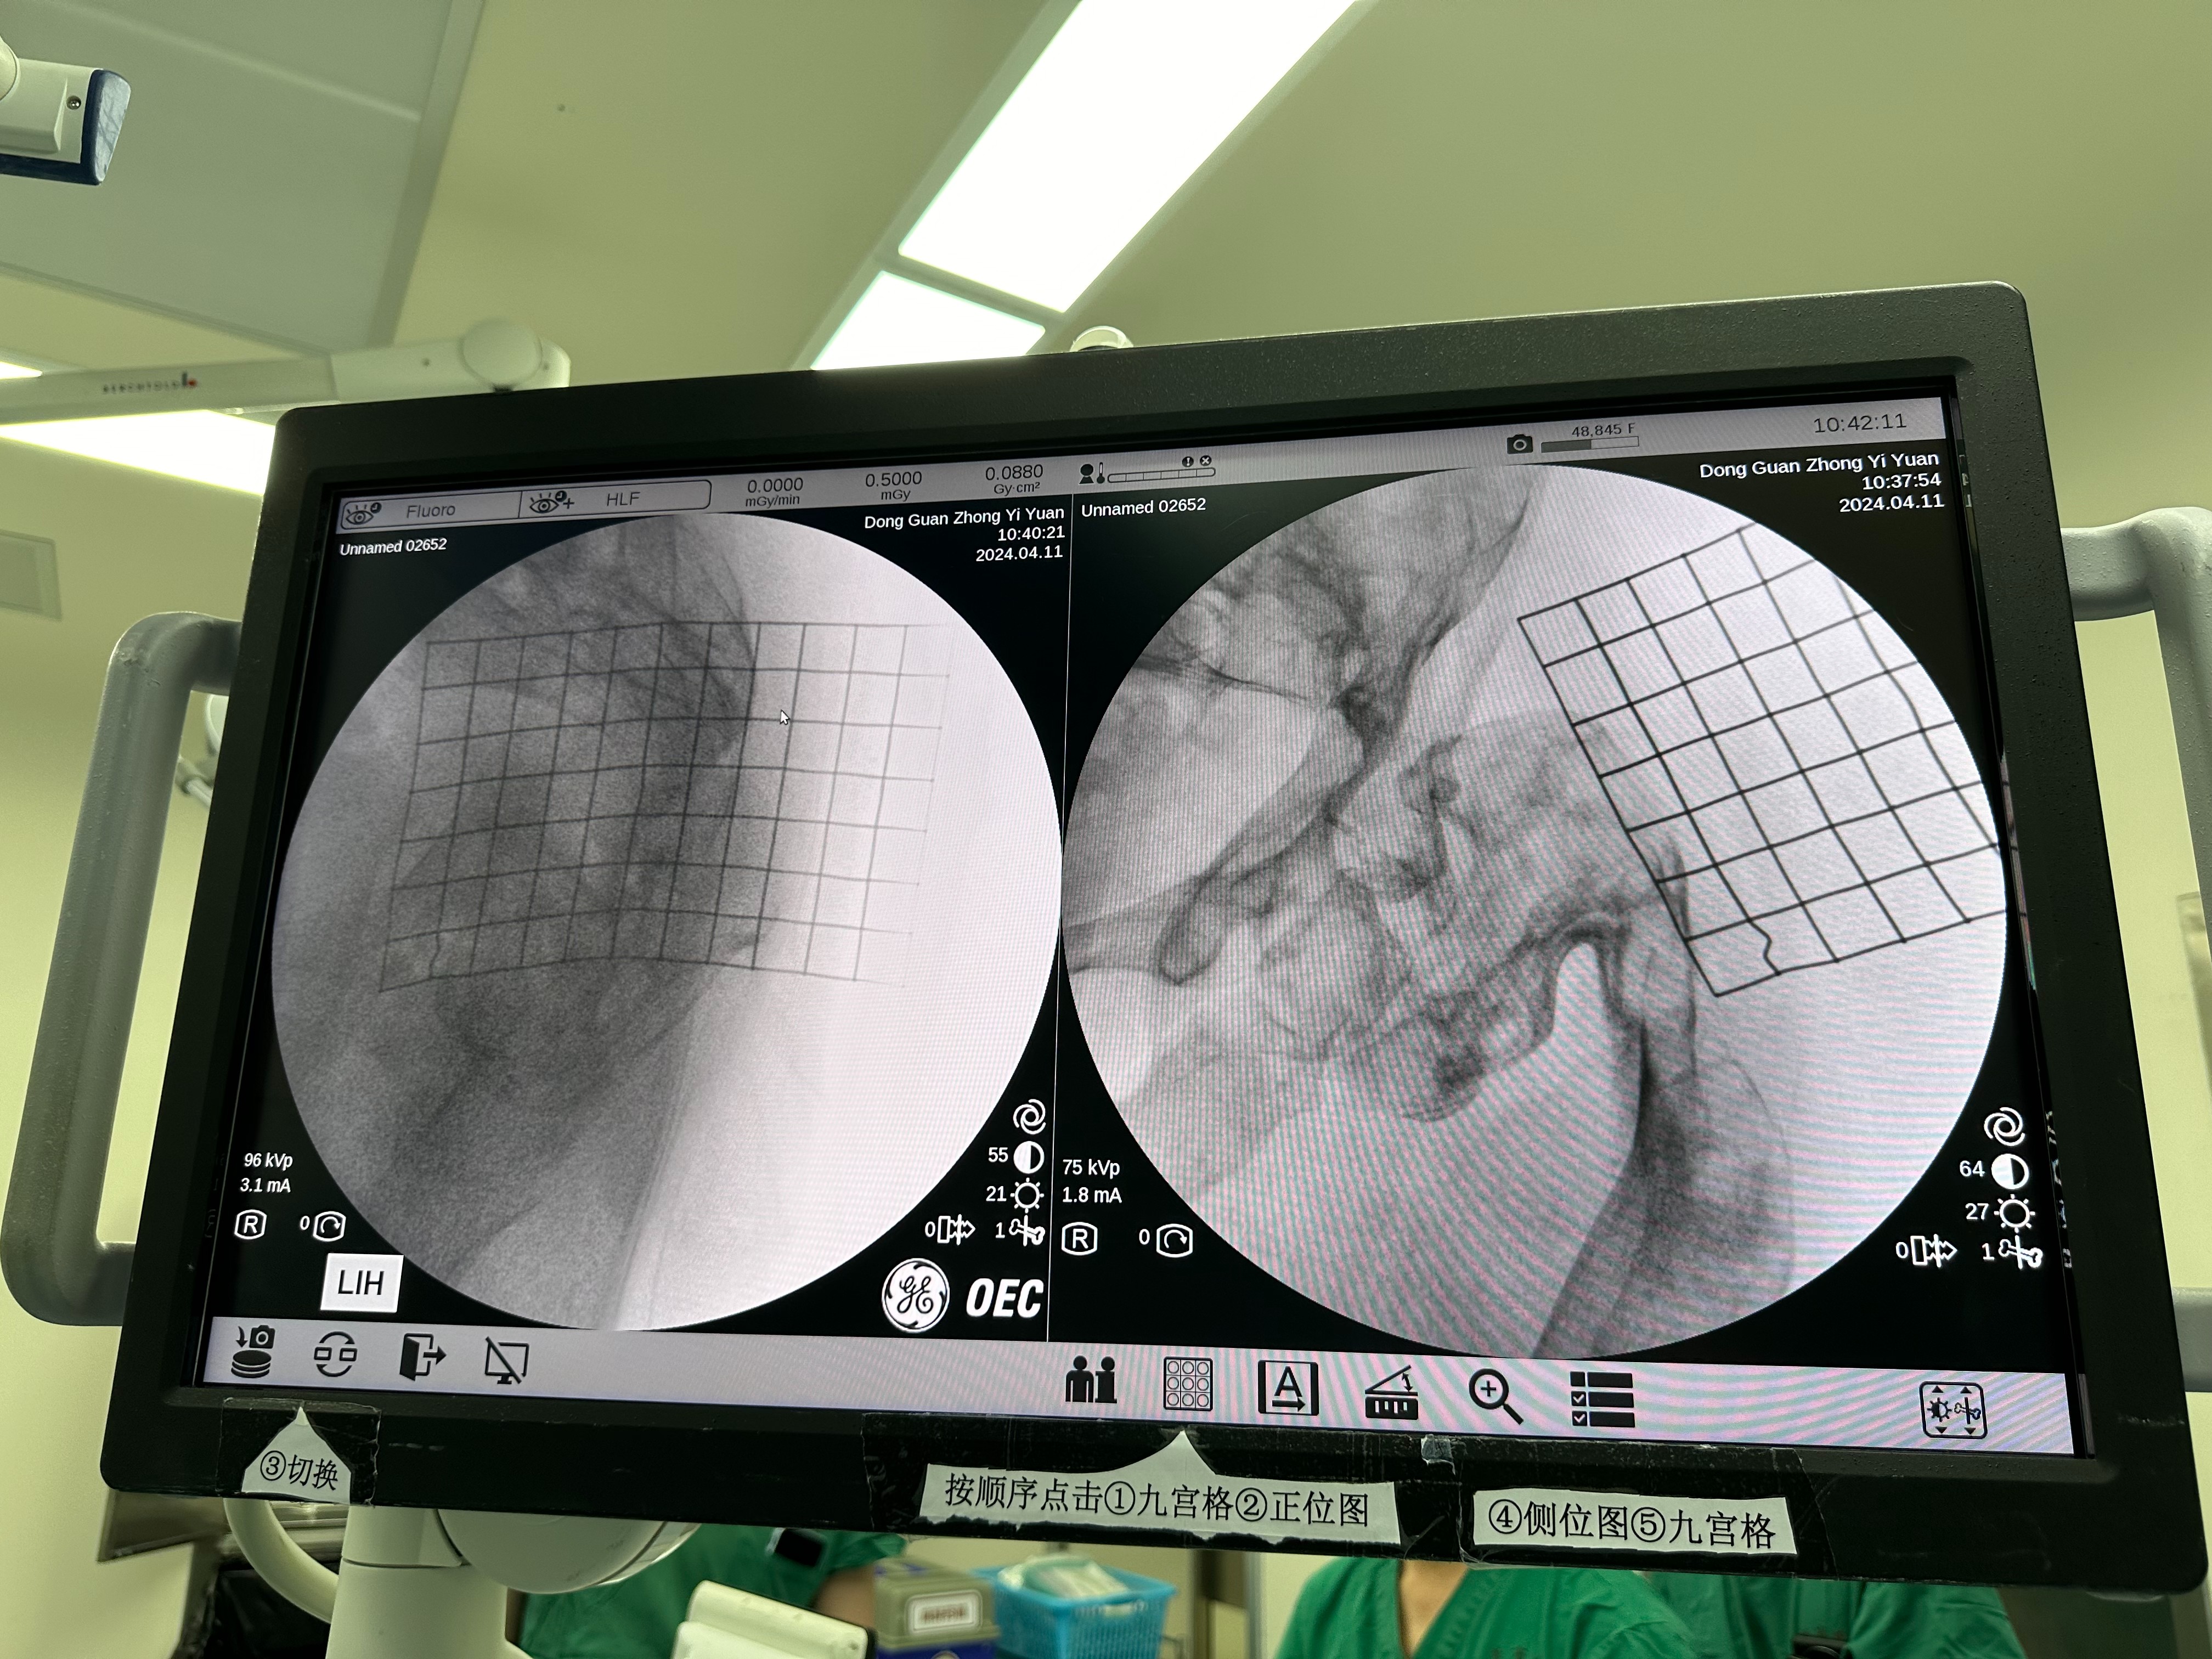

In the morning of April 11th, Prof. Freude performed an intramedullary nail fixation with Director LIANG's team. This surgery is medical treatment for a patient with proximal femur fracture due to osteofibrous dysplasia, and the surgical plan and physical examination were discussed for the patient yesterday.

There was already severe s-shaped deformity in the patient's femur and the cortex of the femur was in minimal quality, and this made both intra-operative imaging to check nail entry and placing of intramedullary nails extremely challenging.

圖片關(guān)鍵詞

During pre-op preparations, Prof. Freude, together with Director LIANG and Director WU Xiankui, measured the position of the greater trochanter using a mesh and identified the nail entry point.

During the operation, Prof. Freude and Director WU worked together to place the intramedullary nails and discussed with Director LIANG about the solutions while there were difficulties in drilling the nails into the fracture. Finally, the femoral fracture was fixed by three elastic femoral intramedullary nails and the operation was successfully accomplished.